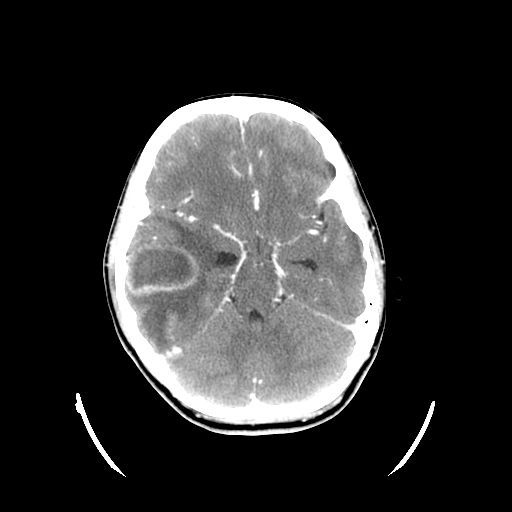

Se realiza una TC craneal urgente con el siguiente resultado: tumoración intraaxial temporal derecha de aproximadamente 39 × 44 mm, con edema perilesional que colapsa asta frontal del ventrículo ipsilateral con dilatación de asa temporal y desviación discreta de línea media con captación de contraste periférica.